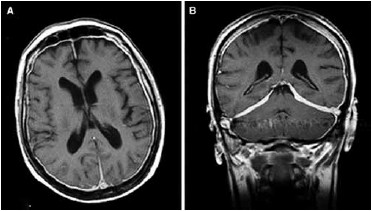

A imagem a seguir refere-se a um homem de 62 anos com queixa de cefaleia crônica, claudicação mandibular e dores articulares difusas. Com base nestes dados e na imagem a seguir, assinale a alternativa correta referente ao possível diagnóstico deste paciente.

(https://link.springer.com/article/10.1007/s00296-007-0504-5)